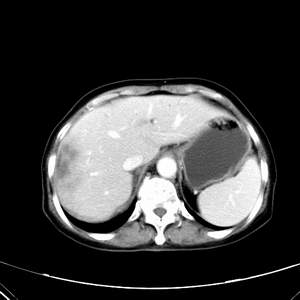

患者,女性,77岁,右上腹胀痛月余。afp正常。ca125升高。即往无肝炎病史。

肝右叶病灶是胆管细胞癌吗?门静脉右支癌栓形成?右侧肾上腺有问题吗?

延时后,病变与肝脏呈等密度,先考虑:肝血管瘤.

渐进性强化,中间见沙砾样钙化,首先考虑血管瘤

病灶渐进性向心性强化,延时病灶中心见条片状高密度影,局部见肝包膜回缩征,结合病人无肝炎病史,考虑肝右叶胆管细胞癌,门脉右支癌栓形成。